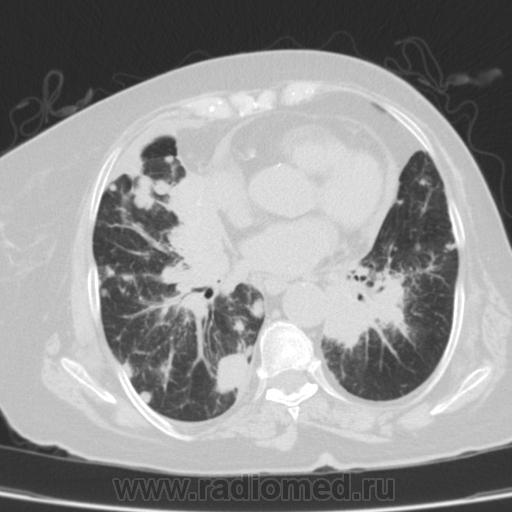

Метастатическое поражение легких.

Пожилая женщина, 76 лет находится на стац.лечении, провели СКТ дообследование.  Сопут- сr левой молочной железы. Такие множественные

поражения  в легких встречаются не часто.

Раннее несколько лет назад оперирована по поводу рака левой молочной железы.